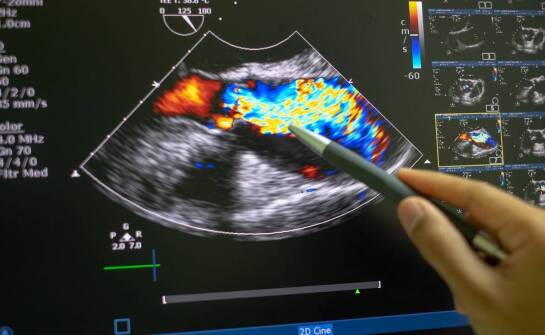

Rola ultrasonografii 3D i 4D w ocenie płodowego serca

Specjalistyczna praktyka położnicza Marka Bliteka wykorzystuje ultrasonografię w diagnostyce prenatalnej, która ma na celu ocenę serca płodu. Ultrasonografia 3D i 4D pozwala na uzyskanie obrazów anatomicznych, co służy ocenie budowy serca oraz funkcji hemodynamicznych. Obejmuje pomiary jam serca, pr